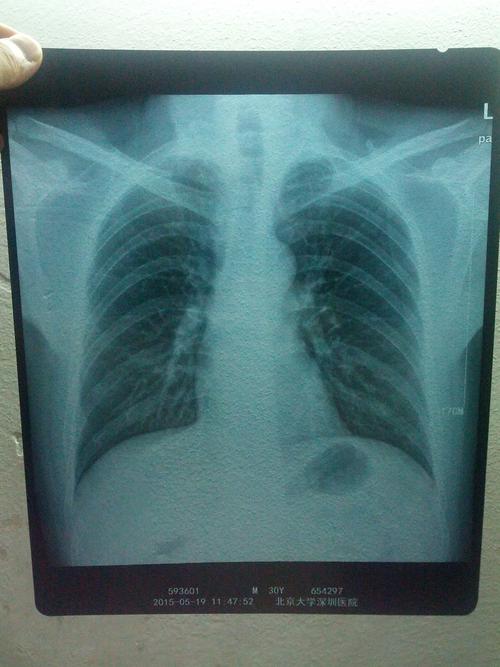

CT对于备孕期的人来说是一个比较重要的检查项目,无论CT检查量多少,都必须要做个全面的检查项目,比如说心肺听诊,肺部彩超等。如果怀孕以后,女性是拍CT过多的话,会有很大的安全隐患,还会影响到腹中宝宝的发育。